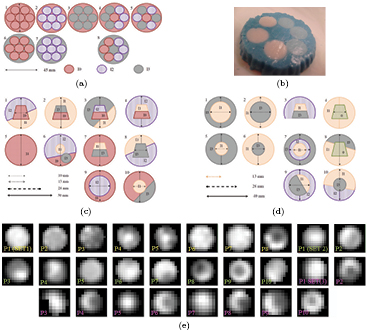

Alginate (Kurth et al 2013) was employed in order to simulate 28 heterogeneous lesions (figure 1). FDG concentrations within the simulated lesions (I3 = 17 kBq ml−1,  ,

) and background (Bg = I3/10) were within the range reported by a previous publication in lung cancer patients (Carles et al 2014). The level of heterogeneity was guaranteed by the coefficient of variance (COV) > 0.3 for all the phantoms (COV , ranging from 0.38–0.64), criteria conventionally applied to identify heterogeneous lesions (Hatt et al 2011). The COVs were computed within VOIideal (see section 2.4) on the static image. All the simulated lesions had a diameter longer than 3 × FWHM (full width half maximum) in order to minimize the partial volume effect (PVE) (Shepherd et al 2012). This restriction is often applied in quantification of intratumoral heterogeneity (Brooks et al 2014, Grootjans et al 2016).

, ranging from 0.38–0.64), criteria conventionally applied to identify heterogeneous lesions (Hatt et al 2011). The COVs were computed within VOIideal (see section 2.4) on the static image. All the simulated lesions had a diameter longer than 3 × FWHM (full width half maximum) in order to minimize the partial volume effect (PVE) (Shepherd et al 2012). This restriction is often applied in quantification of intratumoral heterogeneity (Brooks et al 2014, Grootjans et al 2016).

Figure 1. Heterogeneous inserts made of alginate. (a) SET1. (b) SET1: phantom 8. (c) SET2. (d) SET3. (e) PET static images. Image scale defined by whole image (3D) gray values.

The heterogeneous inserts were placed within a cylindric container filled with an FDG background, Bg. In order to simulate respiratory motion, a Medical Quasar respiratory motion phantom and platform (Dunn et al 2011) were employed (figure 2).

Figure 2. Medical QUASAR respiratory platform (a) and phantom (b).

3.1. Effect of segmentation method

In order to provide some guidance regarding how the TF relate to the heterogeneous activity distribution, in figures 5(a) and (b) we represent the TF derived from the approach to the ideal contour (VOIideal) on the S-image when no movement was applied to the phantoms of SET1. Some of the histograms and co-ocurrence matrix were plotted in figures 5(c)–(j). The results showed that COV values were larger than the criteria to identify heterogeneity (COV > 0.3) for all phantoms. Most of the phantoms were classified as skewed to the right by skewness (SK) and flatter than a Gaussian distribution by kurtosis (KT). Phantom 2 was classified as the most symmetric distribution (SK =−0.005) (see figure 5(d)) and phantom 8 as the most skewed and highly peaked (SK = 0.88, KT = 3.22); see figure 5(f). By comparing the histogram and the corresponding co-ocurrence matrix, it was observed that the spatial information conveyed by the matrix could facilitate the visual assessment of the different layers of FDG concentration.

Figure 5. ((a), (b)): TF derived from the approach to the ideal contour on the S-image for the phantoms of SET1 when no movement was applied. Histograms (c) and co-occurence matrix (d) derived from the approach to the ideal contour on the S-image for phantoms 1 ((c), (g)), 2((d), (h)), 7 ((e), (i)) and 8 ((f), (j)), from left to right. (a) 1st order. (b) 2nd order.